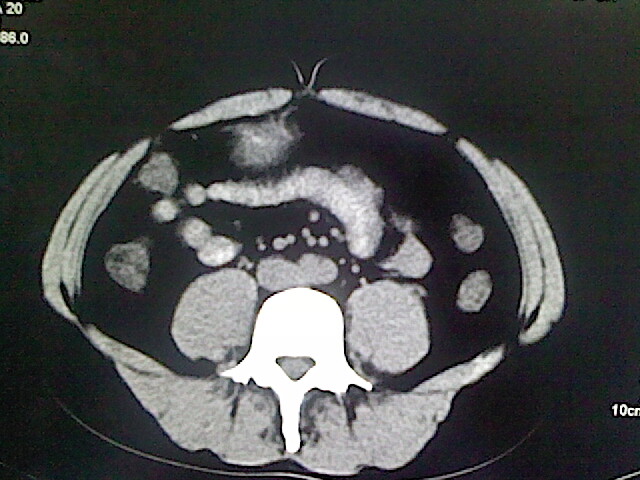

以下是引用卜一在2009-3-14 9:49:00的发言:[br]胆囊萎缩,胆囊壁不规则增厚,内部结构模糊,增强明显强化。另:肝左叶外侧段肝囊肿。支持:慢性胆囊炎!高度可疑:胆囊癌!

以下是引用余辉在2009-3-14 8:48:00的发言:[br]1)慢性胆囊炎。2)肝左叶外侧段肝囊肿。3)脂肪肝。[br]支持,胆囊萎缩,密度增高,不知b超具体有何提示,钙胆汁?结石?

以下是引用jiangjing在2009-3-14 10:18:00的发言:[br]1)慢性胆囊炎。2)肝左叶外侧段肝囊肿。3)脂肪肝。4.】建议行肝功能检查